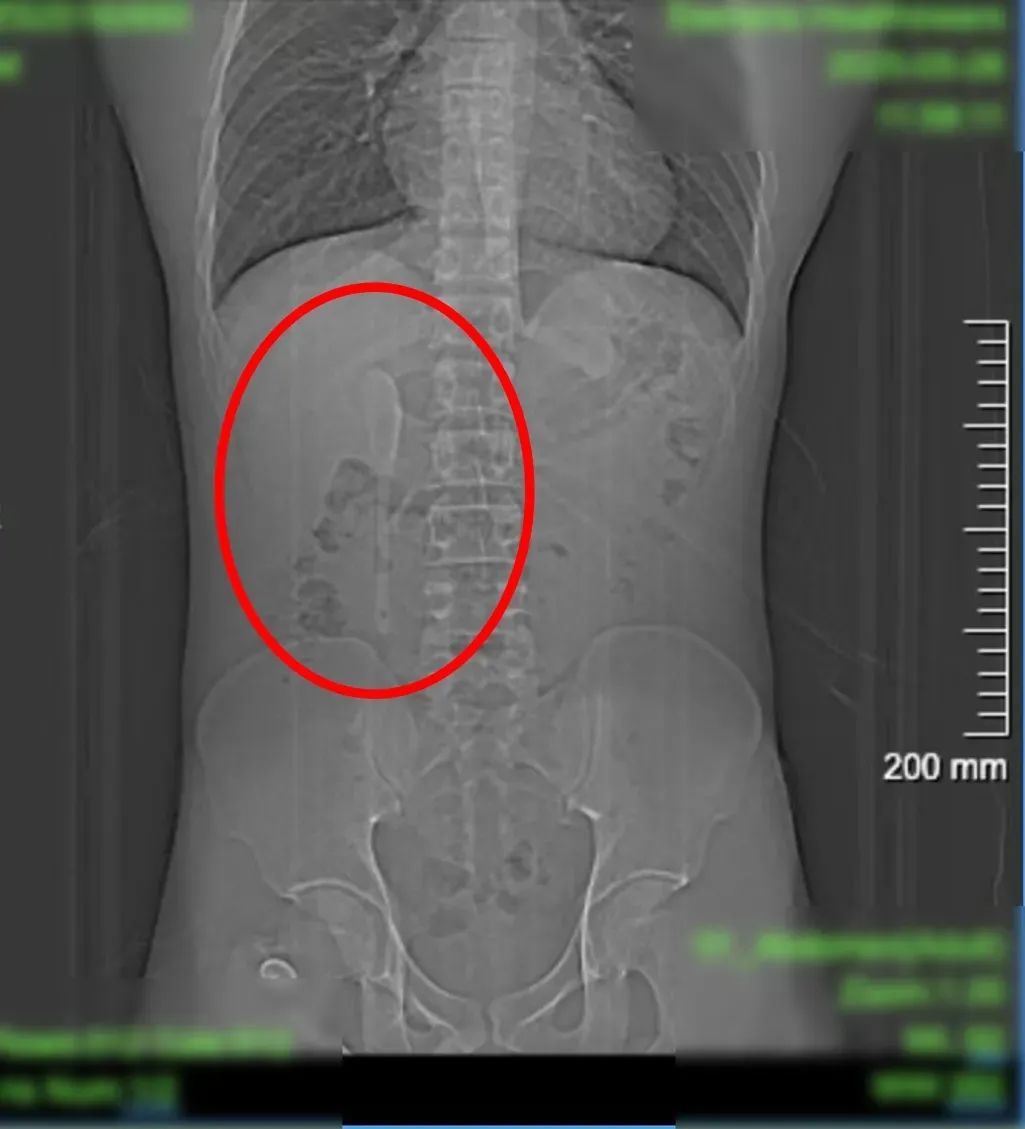

CT显示这支近15厘米长勺状物体

严丝合缝地横亘于

十二指肠球部与降部交界的生理狭窄处

这支被遗忘的勺子,历经6个月胃肠蠕动,最终精准卡进十二指肠球部与降部交界处。此处腔隙狭窄且肠壁极为菲薄,异物极易嵌顿,稍有不慎容易造成穿孔。中山医院内镜中心主任周平红教授解释:“勺子陶瓷质地光滑细长,十二指肠球降交界又是人体上消化道的生理狭窄处,内镜下取出难度极大。若失败,只能开腹手术。”